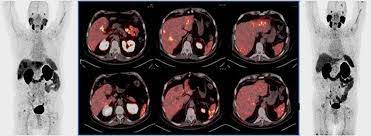

Clinical Characteristics And Prognostic Factors Of Prostate Cancer With Liver Metastases Semantic Scholar

Clinical Characteristics And Prognostic Factors Of Prostate Cancer With Liver Metastases Semantic Scholar from d3i71xaburhd42.cloudfront.net